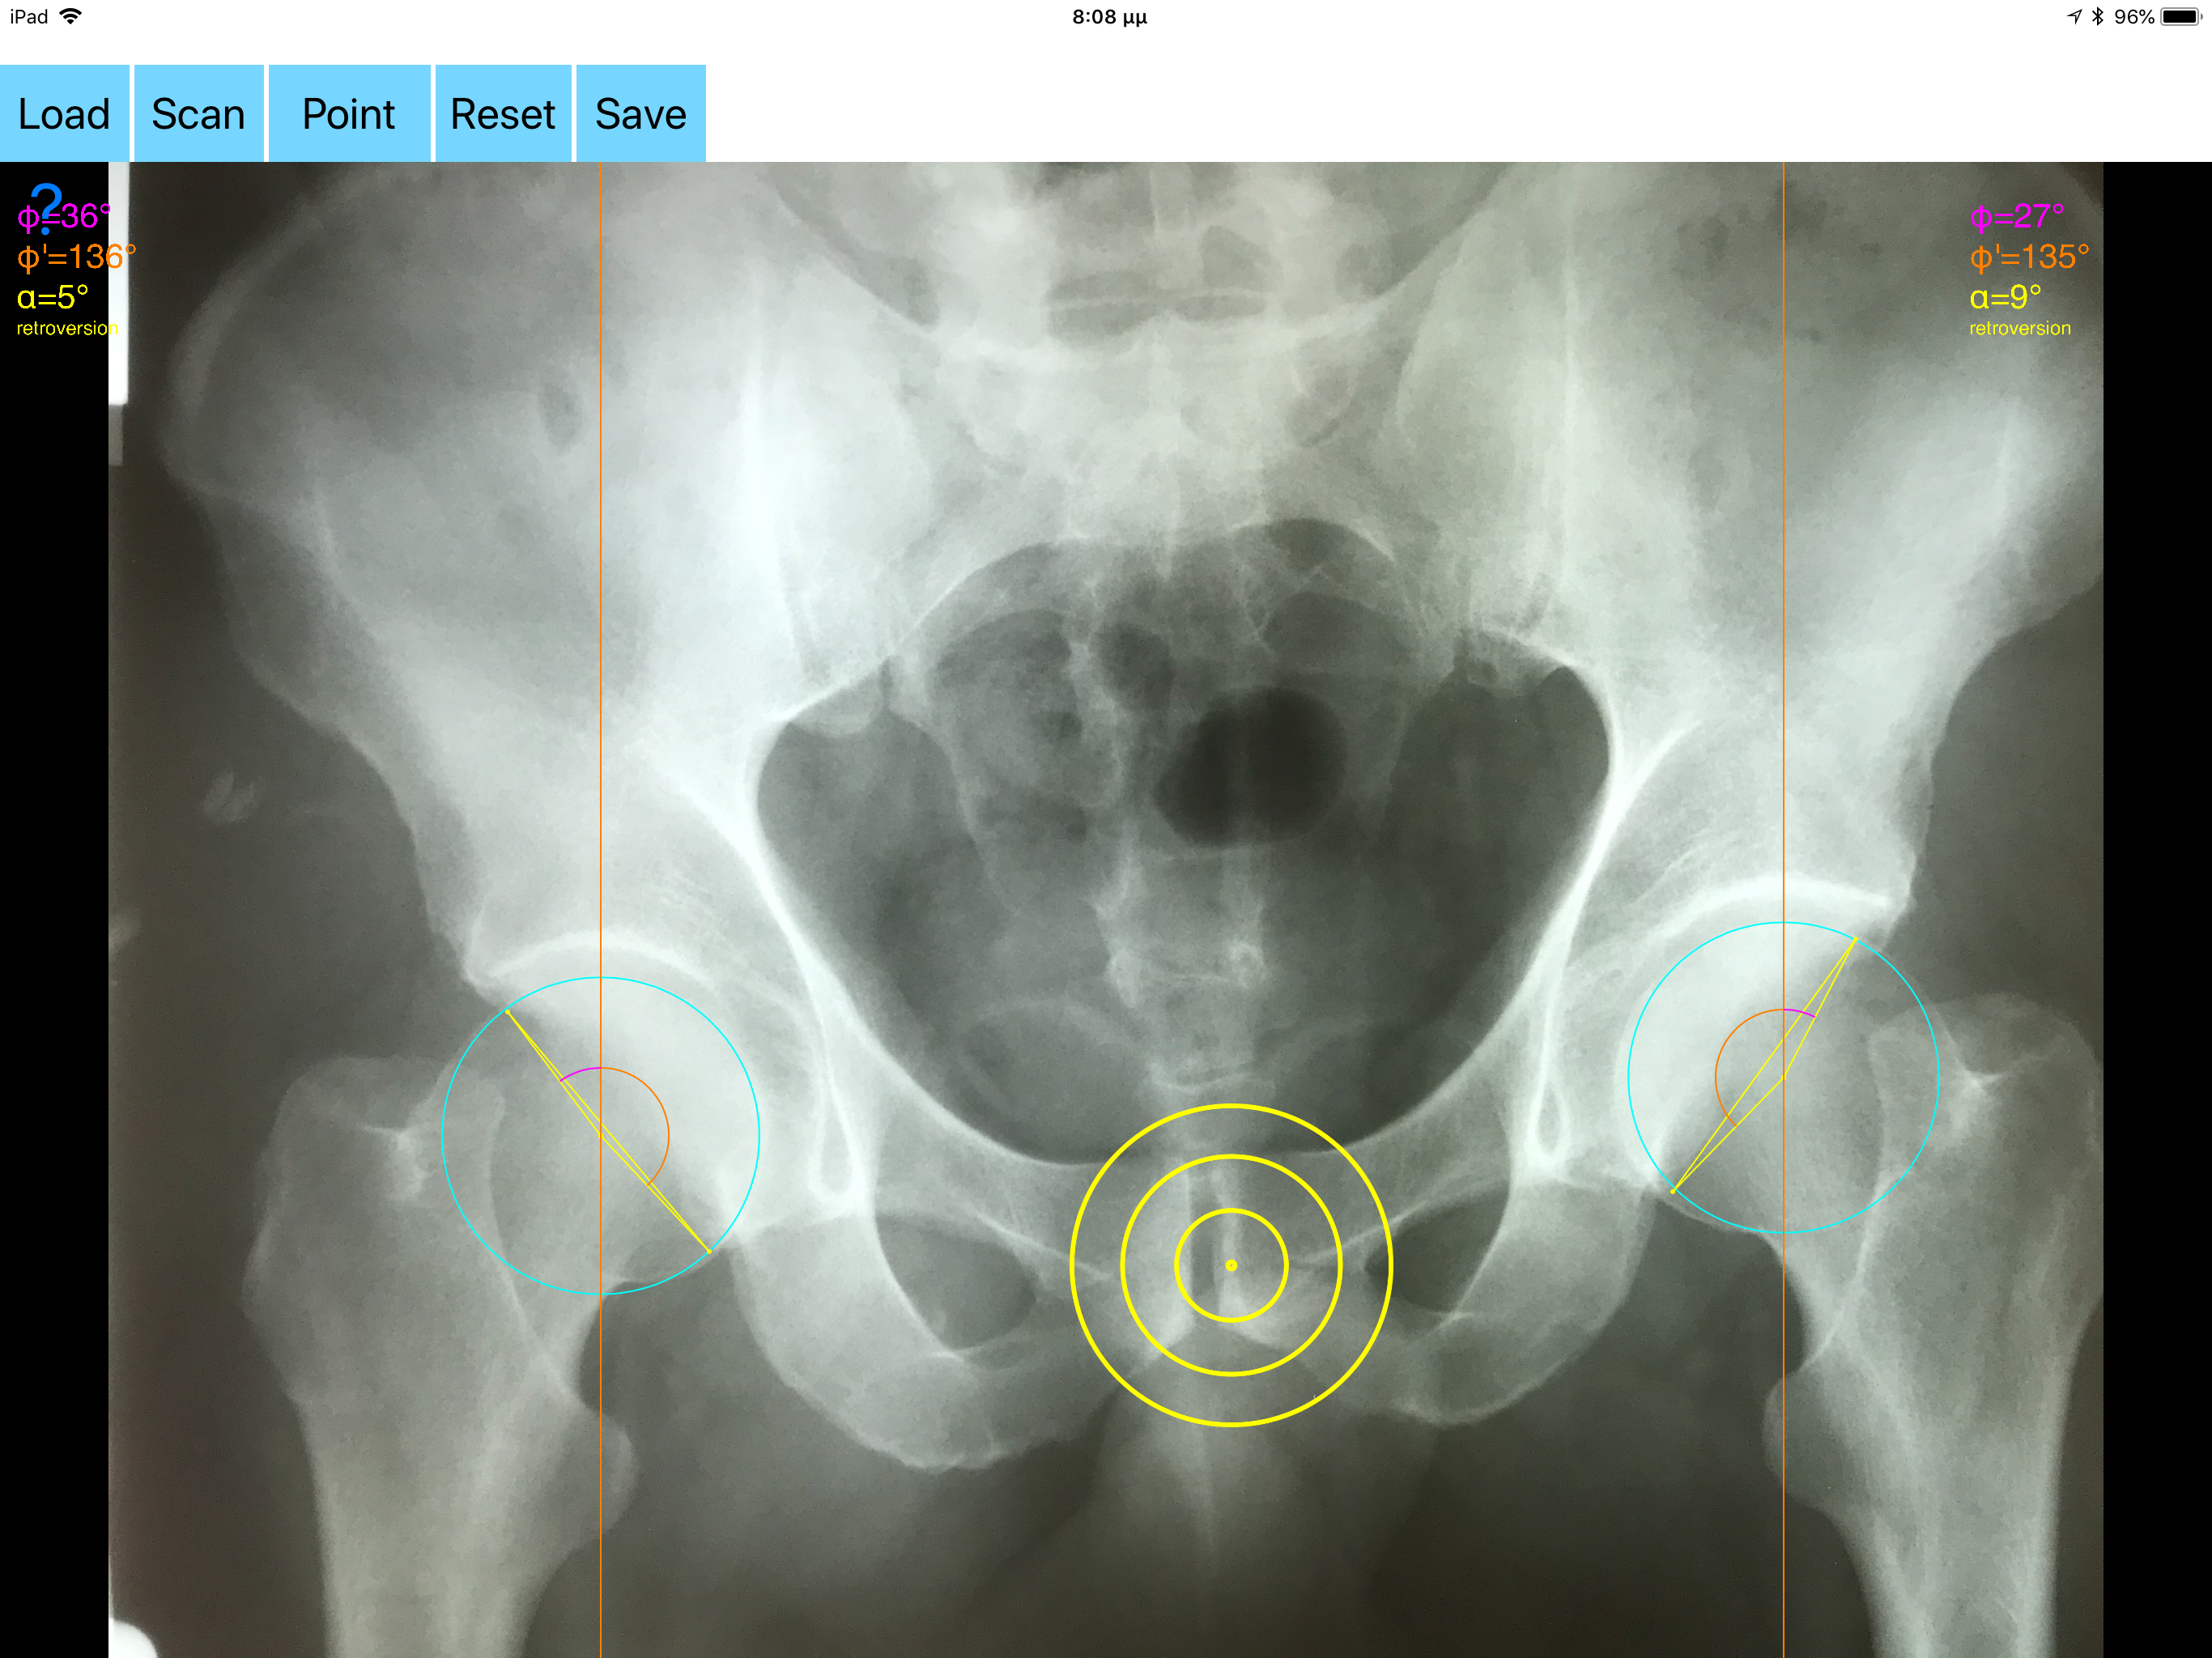

Acetabular version refers to the anteroposterior orientation of the acetabular opening relative to the true horizontal axis of the pelvis. The normal human acetabulum is anteverted in order to allow impingement free range of motion including flexion, adduction, and internal rotation. Abnormal acetabular version has been correlated with pathologic hip conditions including femoroacetabular impingement (FAI) and developmental hip dysplasia.The association between acetabular version and hip pain has been well established in recent years as a source of contributing to early hip osteoarthrosis and labral tears. Recognition and appropriate treatment of abnormal acetabular version is crucial to preventing irreversible damage to the hip Acetabular version is conventionally evaluated on CT scans but excessive radiation doses associated with routine use of computed tomography (CT). An objective radiographic tool which provides measurements comparable in accuracy to CT measurements has been developed by Dr. Hefti (Nomogram).Tedious and time-consuming calculation has to be done in simple X-rays in order to calculate the acetabular anteversion. The primary goal of this App is to help determine radiographic values of acetabular anteversion in a practice in a blink of an eye and avoiding CT scans. The App is medical software aimed for orthopaedic surgeons, providing tools that allow doctors to: -Securely import medical images directly from the camera or stored photos. -By marking certain points in a simple standard AP pelvic radiograph, geometric parameters are being calculated. The App computes the acetabular anteversion based on a pelvic AP radiograph. The angle of anteversion is calculated through the formula according to Heftis nomogram. The acetabular orientation (anteversion/retroversion) is determine by the app by the measurement of the angles between the center of the femoral head and the anterior (φ) and posterior (φ’) acetabular rim. Once you choose correctly the anterior and posterior acetabular rims the app calculates the acetabular anteversion based on nomogram. -The data are printed over to screen so each case can easily assessed -Save the planned images, for later review or consultation. Disclaimer. Regarding its plausibility app offers no diagnosis or treatment. App provide an early indication that further evaluation may be warranted by Speciality Doctor. Explicitly is announced that the apps are not for diagnosis. Clinical judgment and experience are required to properly use the software. App alone do not replace an M.D. or specialist. All information received from the App output must be reviewed before any attempted treatment. The software is not for primary image interpretation. Any influence to the operators in making decisions remains user own responsibility and experience. App does not dispense medical advice. Patient should seek a doctor’s advice in addition using the app and /or before making any medical decisions for themself. Never substitute or replace doctors advice or change treatment modalities based on any measured outcome. App indicated for assisting healthcare professionals for scientific and research reason. Clinical judgment and experience are required to properly use the app and further research and validation is pending in coming future. Reference Friz Hefti, Pediatric Orthopaedics in Practice, Chapter5 , Pelvis hips and thighs 5.3.2.1 Biomechanics of the hip-Book. Springer